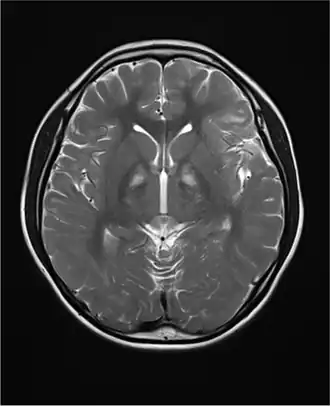

У пациентов с синдромом Кернса — Сейра очень часто обнаруживается церебральная фолатная недостаточность — синдром, при котором уровни 5-MTHF в спинномозговой жидкости снижены, несмотря на нормальные уровни фолиевой кислоты и 5-MTHF в плазме крови[12]. Назначение фолиновой кислоты может в некоторых случаях облегчить симптомы недостаточности и даже скорректировать наблюдаемые на снимках мозга отклонения, особенно если терапия была начата на ранних стадиях заболевания[13]. Предполагаемая причина церебральной фолатной недостаточности у пациентов с синдрмом Кернса-Сейра — дисфункция сосудистого сплетения, нарушающая поступление фолатов в спинномозговую жидкость[14].